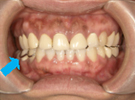

30代女性

事故のため、前歯を2本失いました。

インプラントと矯正治療をしました。

| 治療前 | ||

| インプラント後、仮歯を入れました。 | ||

| 矯正設置を着用し、歯列矯正を行いました。 | ||

| 治療後 | ||